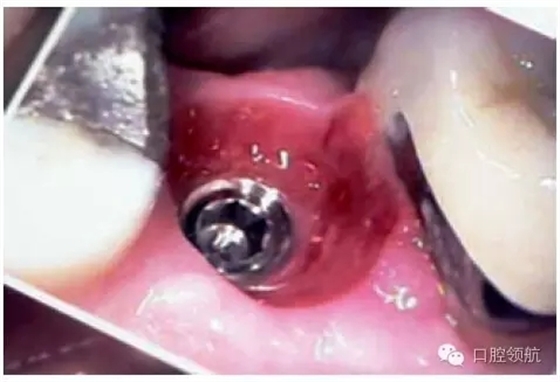

另外一個(gè)方面,深的袖口將妨礙修復(fù)體完全就位(圖9.26)。通常可以通過放射學(xué)檢查,確認(rèn)修復(fù)部件的就位情況,包括種植體與基臺(tái)的連接部分。即使是內(nèi)連接,轉(zhuǎn)移體或者其他修復(fù)部件也會(huì)因深袖口而不能就位。以下技術(shù)可以用于解決這些問題:可以在局部麻醉下,插入喇叭狀或者外展的基臺(tái),以非手術(shù)的方式擴(kuò)大袖口(圖9.27 a,b),然后再通過放射學(xué)檢查確定部件的完全就位。組織會(huì)受壓發(fā)白,15分鐘后,軟組織將會(huì)擴(kuò)張,以允許理想修復(fù)部件的就位,這樣治療將得以繼續(xù)。有時(shí),需要在鄰面做兩個(gè)小切口,以緩解袖口軟組織張力(圖9.28 a,b)。通常不需要縫合。一旦袖口組織塑形完成,可運(yùn)用最佳塑形的臨時(shí)(圖9.29)或最終部件(圖9.30),來維持理想的軟組織外形。

圖9.28 (a)做鄰面切口,使軟組織易于擴(kuò)張,以適應(yīng)外展的愈合基臺(tái)。(b)寬頸愈合帽就位,阻力很小。

圖9.29 由于使用臨時(shí)冠成形,上頜第二前磨牙區(qū)域,組織袖口形態(tài)(卵圓形)良好。